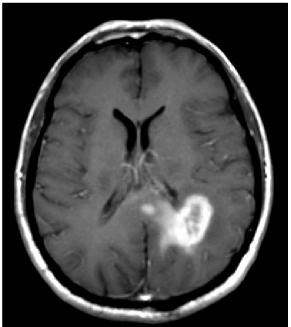

Refer to caption

Figure 1: (a) post-gadolinium T1 weighted image of a glioblastoma located in the left parietal lobe. (b) T2-FLAIR image of the same tumor, showing the surrounding peritumoral edema. (Note that the right side of the image corresponds to the left side of the brain to follow brain imaging conventions.)

The tumor growth calculations are based on MR images routinely acquired in clinical practice. The images incorporated into the simulation process are T1, T2, T2-FLAIR, and T1 post gadolinium. The T1 post gadolinium image shows the vascularized gross tumor volume, and the T2-FLAIR image shows the surrounding edematous region. For illustrative purpose, these two images are shown in figure 1 for a case discussed in detail in this paper.